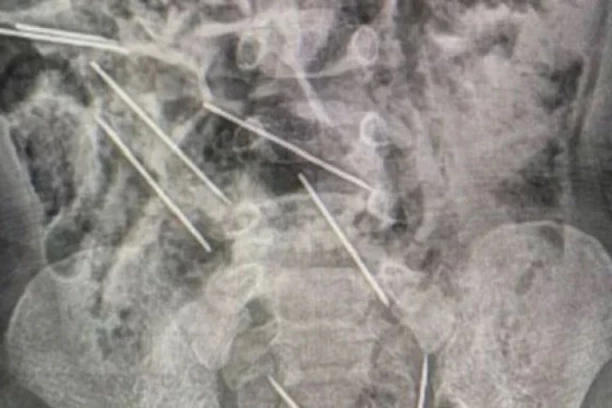

Razonoda 17:54 13.09.2023 “VIDELA SAM SAMO DA IH NEMA”: Majka slučajno otkrila da joj je sin PROGUTAO OSAM IGALA! Usledila je borba za život i veliki obrt